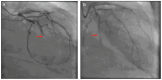

After experiencing syncope, a woman in her 80s with several cardiovascular risk factors presented to the emergency department with shock. The initial troponin was 3,872 ng/L, and the presenting electrocardiogram (ECG) showed a known right bundle branch block (RBBB), but with ST-segment depressions in V1-V2 out of proportion to the patient's baseline RBBB-related secondary repolarization abnormality. After 3 days of hypotension refractory to antibiotics, left heart catheterization was pursued and demonstrated 100% occlusion of the second obtuse marginal artery, confirming the patient had experienced posterior occlusive myocardial infarction (OMI). This case highlights one ECG pattern consistent with posterior OMI in patients with chronic RBBB.